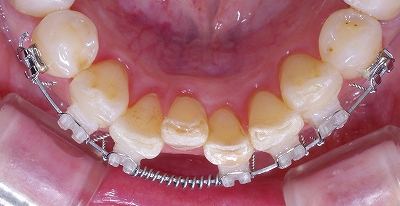

左上側切歯の叢生 その2

その1では前方から見た状態です。

その2はかみ合わせの方向(下から上方に)から見ています。

理想的な位置にきれいに並んでいます。